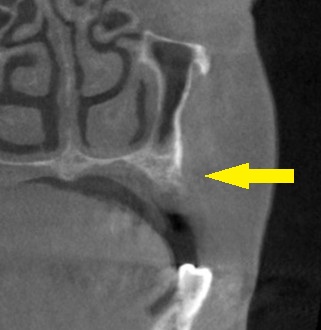

抜歯後3か月でCTを撮ってみたのですが、骨の幅も、高さも足りません(下の写真2段目)。

上方へ少し骨を持ち上げる方法と、頬側には人工骨を補填する方法を併せて行い、インプラント埋入を行なうこととしました。